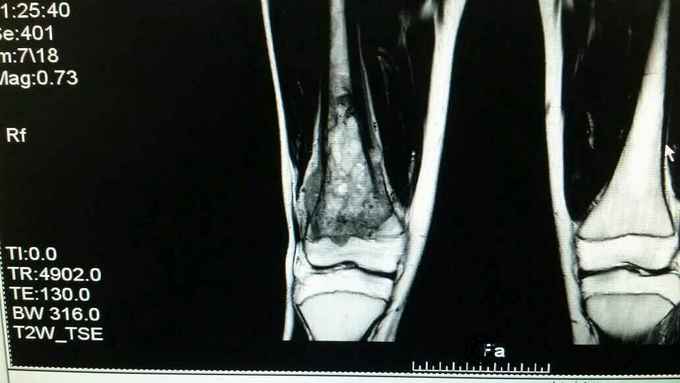

主诉:右大腿疼痛一月余 病史:患者一月前无明显诱因出现右大腿疼痛,未予诊治,自服消炎止痛药物治疗(具体不详),效差,至当地县医院DR示:右股骨远端占位,建议上级医院进一步诊治。

查体:右股骨远端一5cm×3cm大小质硬包块,压痛明显,周围皮温明显升高,患者疼痛拒绝活动。

完善术前各项检查,检验,穿刺活检回示:考虑骨肉瘤,参加省病理会诊及北京积水潭会诊回示:符合骨肉瘤,进行术前新辅助化疗,期间定制肿瘤假体,化疗2个周期后,患者复查磁共振,肿块明显缩小,行右股骨远端骨肉瘤肿瘤膝关节置换术。